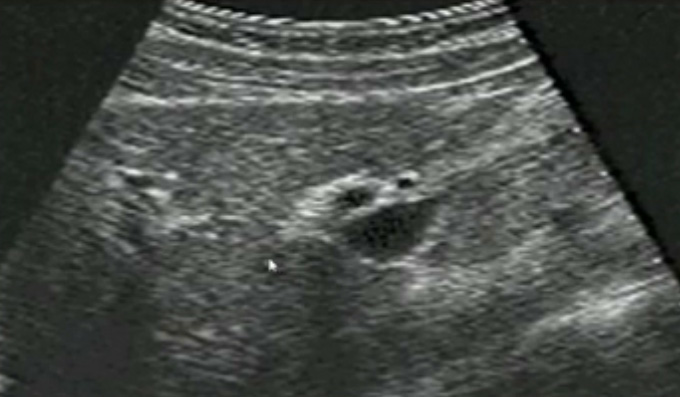

一、正常膽囊超聲圖像有的時候經常發現檢查不到膽囊,其實有幾種可能性,檢查人員的技術不過關沒發現膽囊,就要找上級醫生會診,如果還是沒找到的話就不是技術問題。結石或腫瘤充滿膽囊,使其液腔消失,慢性膽囊炎使得膽囊萎縮或膽囊壁肥厚而囊腔消失患者已進食,膽囊處於膽汁排空的狀態,膽囊先天性過小或缺失;膽囊位置極端異常(可能很低或位於左側)膽囊切除術後(注意詢問病史)。